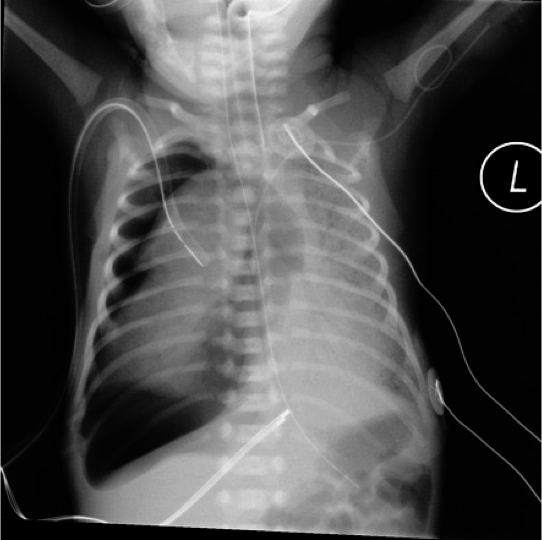

Tension right pneumothorax In Case of Large Pneumothorax

The mediastinum and heart may be pushed to the other side, absent of breath sounds on the ipsilateral side, shifting of cardiac impulse to the contralateral side.